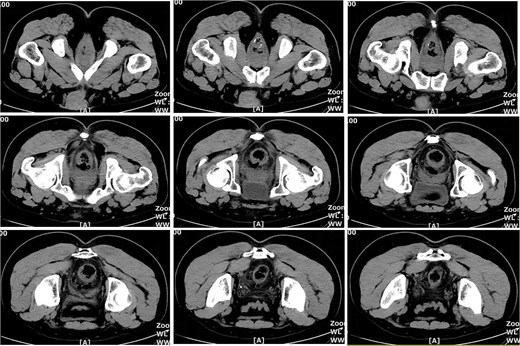

On postoperative Day 7, the patient developed a fever (38.5°C) and mild lower abdominal discomfort. Laboratory tests revealed leukocytosis (white blood cell count: 16.06 × 109/l, neutrophil percentage: 89.1%). A pelvic computed tomography (CT) scan suggested cystitis (Fig. 1). Anti-infective therapy with intravenous cefoperazone sodium and sulbactam sodium was initiated. The patient’s vital signs, complete blood count, and temperature were closely monitored.